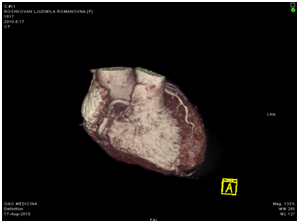

МСКТ коронарных артерий от 08.2010

Ствол ЛКА широкий, имеет ровные контуры, не стенозирован. ПНА в проксимальном сегмента имеет неровные контуры за счет кальцинированных и частично кальцинированных бляшек, просвет артерии на этом уровне сужен до 30-50%, в среднем сегменте определяется ряд пристеночных и циркулярных мягких бляшек, со стенозом артерии до 60-75%, дистальные отделы артерии малого калибра, плохо заполняются контрастным веществом. ОА нормального диаметра, заполняется контрастным веществом без признаков гемодинамически значимого стеноза. ПКА нормального диаметра, в проксимальном сегменте имеются смешанные частично кальцинированные бляшки, стенозирующие просвет до 30%, в среднем сегменте визуализируется пристеночная смешанная бляшка, стенозирующая просвет до 50-70%, дистальный сегмент не изменен. Правый тип коронарного кровоснабжения.